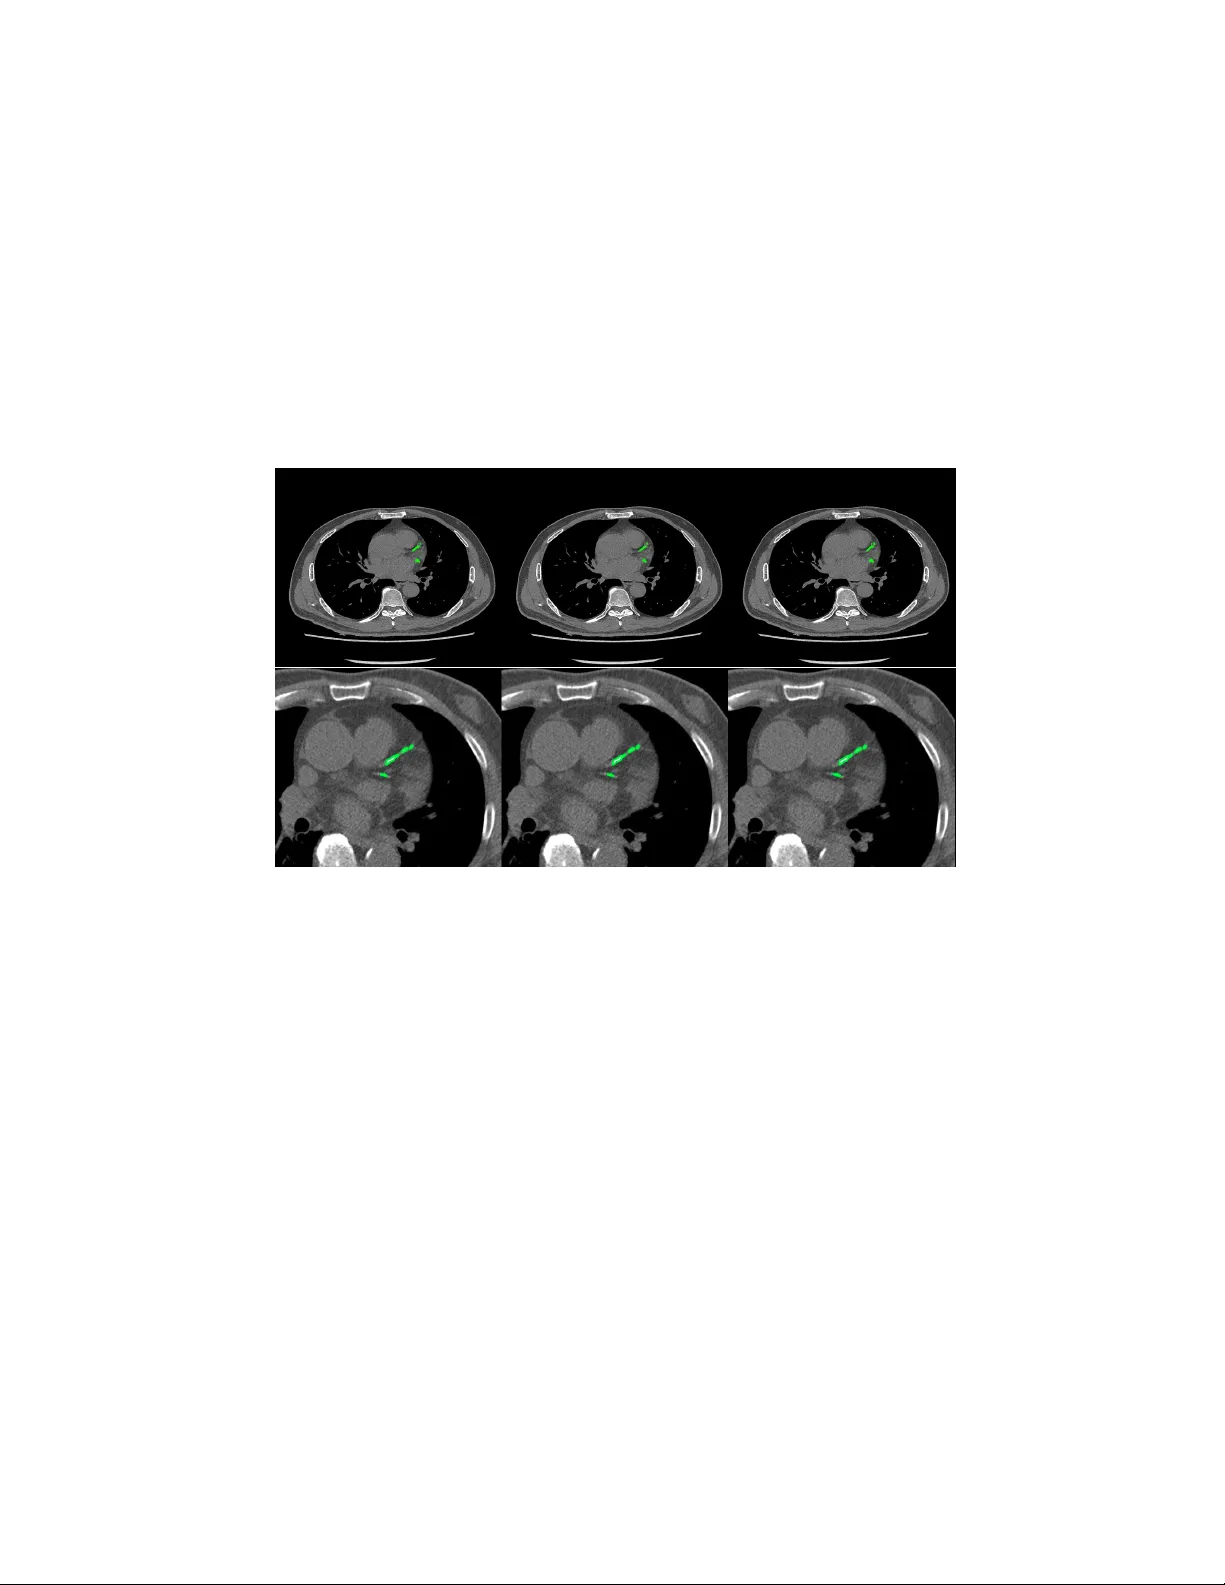

Automatic Calcium Scoring in Cardiac and Chest CT Using DenseRA Unet Jiec hao Ma and Rongguo Zhang Infervision Inc. Abstract. Cardio v ascular disease (CVD) is a common and strong threat to h uman b eings, featuring high prev alence, disabilit y and mortality . The amoun t of coronary artery calcification (CAC) is an effectiv e factor for CVD risk ev aluation. Conv entionally , CAC is quantified using ECG- sync hronized cardiac CT but rarely from general c hest CT scans. How- ev er, compared with ECG-synchronized cardiac CT, chest CT is more prev alen t and economical in clinical practice. T o address this, w e propose an automatic metho d based on Dense U-Net to segmen t coronary calcium pixels on b oth types of CT scans. Our contribution is tw o-fold. First, we prop ose a no vel netw ork called DenseRAUnet, which tak es adv an tage of Dense U-net, ResNet and atrous conv olutions. W e prov e the robustness and generalizabilit y of our mo del by training it exclusively on chest CT while test on both types of CT scans. Second, we design a loss function com bining b ootstrap with IoU function to balance foreground and bac k- ground classes. DenseRAUnet is trained in a 2.5D fashion and tested on a priv ate dataset consisting of 144 scans. Results sho w an F1-score of 0.75, with 0.83 accuracy of predicting cardiov ascular disease risk. Keyw ords: Calcium scoring · deep learning · Cardiac CT · Chest CT · Agatston score · Conv olutional neural net work. 1 In tro duction Cardio v ascular disease (CVD) has b ecome one of the most high-mortalit y dis- eases, for whic h the amount of coronary artery calcification acts as a strong indicator of CVD risk [1]. In clinical practice, CA C is quan tified b y the Agat- ston score, using dedicated cardiac CT scans, follo wed b y a expert who man ually iden tify CA C lesions. T o assist medical professionals, previous w ork based on classical machine learning ha ve attempted to design CAD methods for computation of CAC score. Durlak et al. [2] applied an atlas-based feature approac h in combination with a random forest classifier whic h is used to incorporate fuzzy spatial kno wledge from offline data. Isgum et al. [3] emplo yed a nearest neighbor classifier directly and a tw o-stage classification with nearest neigh b or as well as supp ort v ector mac hine classifiers. There are plent y of other researc h can b e explored [4,5,6]. In recen t years, conv olutional neural net works (CNNs) hav e exhibited great success in Computer Vision by data-driven, esp ecially in image classification 2 Jiec hao Ma and Rongguo Zhang tasks. Mean while, fully con volutional netw orks (FCNs) , as the extension of CNNs, also obtained state-of-the-art p erformance for segmentation problems. In the context of medical image segmentation, sp ecifically cardiac calcification seg- men tation, algorithms based on deep learning ha ve shown promise. W olterink et al. [7] first attempted to apply CNNs to CAC scoring in con trast-enhanced cardiac CT, with a tw o-stage netw ork structure but only one stage using deep learning. Recen tly , some w orks used t wo-stage deep learning structure [8,9], with the first stage identifying CAC-suspected vo xels and the second stage more pre- cisely identifying CAC. Shadmi et al. [10] emplo yed Dense-FCN, a design differ- en t from the tw o-stage methods, to segmen t the lesion directly in cardiac CT. But all the automatic CAC scoring approaches ab o ve are designed for either cardiac or c hest CT only . More recen tly , m ultiple screening in one CT session has b ecome a trend in clinical practice. Huang et al. [11] presented an automatic metho d with t wo CNNs that p erforms direct computation of CAC score in b oth cardiac and chest CT scans. On the other hand, according to the work of W olterink et al. [9], 2.5D input has a great adv antage compared with 3D input in CAC scoring, as the n umber of parameters are greatly reduced while retaining spatial information. Both Lessmann et al. and wolterink et al. [8,9] used the 2.5D Con vNets com- bining features from three identical 2D ConvStac ks with shared w eights, eac h pro cessing an input patc h from a differen t orthogonal viewing direction (axial, sagittal and coronal). T o our kno wledge, none hav e applied the efficien t 2.5D F CN arc hitecture on multiple types of non-enhanced CT. In this w ork, we prop ose an automatic method for CAC scoring on b oth ECG-sync hronized cardiac and chest CT. Unlike the the metho ds required tw o cascaded netw orks to calculate CA C scoring, our net work directly segment the calcified vo xels and obtain CAC scoring. Meanwhile, we adopt a 2.5D patch input to reduce the computational ov erhead of 3D input. Instead of previous 2.5D metho ds [8,9]which input patc h from axial, sagittal and coronal direction, our netw ork tak es 9-channel stacks of images with corresp onding 2D labels for segmen tation of the corresp onding center slice. W e applied our metho d on a priv ate dataset comp osed of 44 Cardiac CT scans and 805 chest CT scans. In comparison to exp erts’ manual annotations, our algorithm achiev ed comp etitive results. 2 Materials and Metho ds 2.1 Data A dataset of 849 CT scans w as collected from several medical cen ters in China, whic h consists of 805 chest CT scans and 44 cardiac CT scans. The CT scans w ere acquired b y different CT scanners with Philips, GE and Siemens. Each CT scan contains a sequence of slices at the thin-section slice spacing (range from 1.0 to 3.0 mm). CAC lesions were manually labe led b y three exp erienced radiologists from differen t cen ters. Automatic Calcium Scoring in Cardiac and Chest CT Using DenseRAUnet 3 W e newly connected 144 CT scans as a test set, incorporating c hest CT scans and cardiac CT scans from medical centers in China. And to ev aluate our net work p erformance, lesions w ere delineated by exp erienced radiologists. 2.2 Data preprocessing Since the connected dataset con tains v arious sizes of chest CT scans and cardiac CT scans, w e process all images as follows. First, w e resize all CT images to 512 × 512 pixel resolution. Second, we randomly crop and then resize images to 512 × 512, where maximum size of the cropped image is 256 × 256. W e con tinuously select nine pro cessed slices as the input of our net work, and for such an input, its lab el is the ground-truth lab el of its middle slice. W e also pro cess all ground- truth lab els to alter the pixel lab el when its corresp onding CT v alue low er than 130HU. 2.3 DenseRA Unet for segmen tation W e prop osed a no vel F CN architecture based on dense U-Net for calcification segmen tation, called DenseRA Unet. The netw ork consists of tw o main comp o- nen ts: (1) a basic netw ork for feature extraction, and (2) three task-specific sub-net work structures, incorporating R esidual A tr ous Unit (RAU) , scSE blo ck and Extr a Dense Blo ck (EDB) . Fig. 1 depicts our prop osed DenseRAUnet. Dense Block 1 Dense Block 2 T Dense Block 3 T Dense Block 4 T upsample block2 upsample block3 !" sample block 1 scSE scSE scSE RAU RAU RAU EDB upsample block Atrous Conv Dilation=2 Atrous Conv Dilation=4 Atrous Conv Dilation=8 BatchNorm BatchNorm BatchNorm ReLU ReLU ReLU Concact + X Identity F(X)+X Residual Atrous Unit Conv Deconv , 3 # 3 Conv , Relu T T ransition Layer Input Output Concat Avg-pooling 2 ×2 Fig. 1. The ov erall structure of DenseUnet and details in Residual Atrous Unit The basic net w ork is an enco der-deco der architecture, similar to dense U-Net. W e adopt a bac kb one netw ork (DenseNet-121) as the enco der sub-netw ork. The deco der sub-netw ork consists of three deco der modules. Each deco der mo dule is 4 Jiec hao Ma and Rongguo Zhang an upsampling blo c k follow ed by a scSE blo c k, where upsampling block contains a deconv olution la yer and tw o conv olution la yers, which follow ed by a Batch Normalization (BN) la yer and an activ ation function called ReLU. Residual A trous Unit. Accurately segmenting v arious sizes of calcified areas ma y require differen t com binations of local and global information. So w e con- sider that a simple skip connection is not enough for the complex segmen taiton task. Inspired by ASPP [12] and embed the idea of Inception [13], we further design a lateral connection called Residual Atrous Unit (RAU). Suc h a mo dule is a residual blo c k, and is used to capture multi-scale information b y combining sev eral conv olutional lay ers with differen t dilation rates in parallel. As shown in Fig.1, we use a concatenation of three 3 × 3 dilated conv olution la yers with dilation rates are 2, 4, and 8 in each RA U. scSE blo ck. T o take full adv an tage of lo cal and global information, w e added scSE blo ck in the deco der sub-netw ork, whic h is in tro duced in [14] for recali- brating the feature maps separately along c hannel and space. Extra Dense Blo c k. In order not to waste the image features extracted from input images, we insert an Extra Dense Blo ck (EDB) in the first skip connection. Suc h a blo c k could make more accurate use of shallo w information, which do not represen t input image in a high dimensional space, via adding more nonlinear in to the first long connection. 2.4 Loss F unction In ter-class imbalances are common problems when using deep learning metho ds for image segmentation, and even more in me dical image segmentation. T o solve it, w e prop ose a new loss function, the com bination of Bo otstrap Loss and IoU Loss: Loss = B ootstr ap Loss + I oU Loss (1) Bo otstrap Loss. When we train a FCN, though images were cropped, there ma y b e thousands of lab eled pixels to predict. How ev er, many of them may b e easily distinguishable, and con tinuing to learn from these pixels do es not impro v e mo del p erformance. In the context of medical image segmentation, most of such pixels are mark ed as bac kground. F or this reason, w e design a weigh ted b o otstrap loss, whic h not only forces net work to fo cus on hard pixels but also balances p ositiv e and negativ e pixels during training. Supp ose there is only one processed image p er mini-batc h and there are a total N pixels to predict. There are only tw o categories c j in the lab el space. Let y i denotes the ground-truth lab el of pixel x i , and p i,j denotes the predicted probabilit y that pixel x i b elongs to the category c j . Then, the loss function could b e defined as: l = −      α P i ∈ N ,j =0 log p i,j 1 { p i,j < t and y i = j } P i ∈ N ,j =0 1 { p i,j < t and y i = j } + β P i ∈ N ,j =1 log p i,j 1 { y i = j } P i ∈ N ,j =1 1 { y i = j }      (2) Automatic Calcium Scoring in Cardiac and Chest CT Using DenseRAUnet 5 where t is a threshold. Here 1 {·} is equal to one when the condition in parenthe- ses, and otherwise is zero. In other words, we fo cus all p ositive pixels and drop negativ e pixels when they are too easy for the curren t mo del, i.e. their predicted probabilit y greater than t . In practice, we hope that positive and negative pixels are balanced, hence we add α and β as trade-off co efficients. IoU Loss. Bootstrap loss is similar to cross en tropy loss, focusing more on its o wn predictions of pixels and ignoring the relationship b et ween adjacent ones. T o b etter obtain the boundary of lesion, w e add IoU in the loss function using suc h a relationship. Supp ose there are N pixels to predict. T o ensure that losses are on the same magnitude, we use the following exp onen tial form of IoU: iou l oss = − ln P i ∈ N p i g i P i ∈ N p i + P i ∈ N g i − P i ∈ N p i g i (3) where p i is the predicted probabilit y of pixel x i , g i is the ground-truth lab el of pixel x i . 2.5 P ost-pro cessing The final segmentation result of the netw ork is obtained b y a predefined thresh- old (here set to 0.5), and each lesion segmented b y the netw ork is considered a calcification candidate. Then each candidate is classified as CA C b y thresholding with 130 HU and p erforming connected-components analysis. Since the CT slice thic kness is mostly 1mm, calculation of the final Agatston score for the whole v olume is done b y the following corrected form ula: Ag atston S cor e = X i X n f i,n A i,n ∆S 3 (4) where i is the i th CT slice of a CT volume, n is the n th selected lesion, f is the weigh ted intensit y , A is the lesion area, and ∆S is the slice spacing (mm). 3 Exp erimen ts and Results Ev aluation Metric. W e ev aluate the pixel-level segmentation pe rformance of the netw ork by F1 score: F 1 = 2 · P r ecision · Recal l P r ecision + Recal l (5) W e also define CAC r ate denotes the prop ortion of patien ts who w as correctly predicting the CVD risk level without p ost-processing, and CA C filter R ate rep- resen ts the prop ortion of patien ts with p ost-pro cessing. Implemen tation details. The exp erimen ts conducted were all trained from scratc h and initialized b y the Gauss metho d. During training, w e collected one pro cessed image as a mini-batch for each iteration and trained for 25 ep ochs. T o 6 Jiec hao Ma and Rongguo Zhang optimize these experiments with fast conv ergence, w e employ ed the SGD opti- mizer with momentum of 0.9. The initial learning rate is 0.001 and is reduced b y 0.99 times per 2000 iterations. The parameters in the loss function are exp er- imen tally set as t = 0 . 9, α = 8 and β = 1. W e implemen ted all the exp eriments via the deep learning toolki MXNet and trained on a GTX 1080 (NVIDIA) GPU. Ablation exp erimen ts. W e use “Dense U-net & Bo otstrap Loss” as the base- line for all exp eriments. T o ev aluate the effectiv eness of v arious structures in our metho d, we conducted ablation exp erimen ts. First, using the b o otstrap loss, w e compare the role of three mo dules in the netw ork. Second, we studied the effect of tw o loss functions through trained our netw ork. T able 1. Comprasion of p erformance of the basic netw ork using different tricks Basic network Bo otstrap RA U EDB scSE IoU F1-Score Dense U-Net √ 0.65 √ √ 0.68 √ √ √ 0.69 √ √ √ √ 0.71 √ √ √ √ √ 0.75 Ours T able 2. Qualitativ e results of CAC rate and CA C filter rate for patients, Patien ts represen ts the total num b er of patients, CA C No. and CA C fliter No. represents the n umber of patients w ere predicted correctly by model and p ost-processing resp ectively . T ric ks CAC No. CAC filter No. Patien ts CAC Rate CAC filter Rate Dense U-net 101 99 144 0.70 0.69 Dense U-net+RAU 104 111 144 0.72 0.77 Dense U-net+RAU+EDB 109 115 144 0.76 0.80 Dense U-net+RAU+EDB+scSE 109 117 144 0.76 0.81 Our prop osed metho d 113 120 144 0.78 0.83 T able 1 lists the F1 scores of Dense U-Net using different tricks, T able 2 indicates the performance of corresp onding netw ork arc hitectures in T able 1 on CA C. It is sho wn that all the tric ks provide increase in F1 score and CAC in comparison to the baseline. W e further observ e that adding RA U in the net work ac hieves more significant improv emen t for CAC segmen tation. Comparing the results across T able 1, our metho d yields the best p erformance. F rom T able 2 w e can also conclude that p ost-processing b y the definition of CA C score is essential. 4 Conclusion This paper prop osed an algorithm based on deep learning. Our method consists of t wo core elements: (1) a no v el fully con volutional netw ork, DenseRA Unet, and Automatic Calcium Scoring in Cardiac and Chest CT Using DenseRAUnet 7 (2) a loss function combined b ootstrap loss and IoU. W e trained our netw ork in a 2.5D-patc h fashion to reduce input parameters while preserving spatial information. While trained solely on chest CT, our mo del achiev ed comp etitiv e and robust p erformance on b oth chest CT and cardiac CT which has significant higher resolution and lo wer spacing compared to training data, thanks to the p o w er of residual atrous unit that enlarges the receptiv e field with down ward compatibilit y . W e aim to futher explore and extend our method to other medical image analysis c hallenges in future w ork. Fig. 2. Segmentation results of chest CT (top) and cardiac CT (b ottom). F rom left to righ t: the segmen tation result of our mo del without p ost-processing, the result of with p ost-processing, ground truth. References 1. John A Rum b erger, Bruce H Brundage, Daniel J Rader, and George Kondos. Electron beam computed tomographic coronary calcium scanning: a review and guidelines for use in asymptomatic persons. In Mayo Clinic Pr o c e e dings , volume 74, pages 243–252. Elsevier, 1999. 2. F elix Durlak, Michael W els, Chris Sch wemmer, Michael S ¨ uhling, Stefan Steidl, and Andreas Maier. Growing a random forest with fuzzy spatial features for fully automatic artery-sp ecific coronary calcium scoring. In International Workshop on Machine L e arning in Me dic al Imaging , pages 27–35. Springer, 2017. 3. Iv ana Isgum, Mathias Prokop, Meindert Niemeijer, Max A Viergev er, and Bram V an Ginneken. Automatic coronary calcium scoring in lo w-dose chest computed tomograph y . IEEE tr ansactions on me dic al imaging , 31(12):2322–2334, 2012. 8 Jiec hao Ma and Rongguo Zhang 4. Uda y Kurkure, Deepak R Chitta jallu, Gerd Brunner, Y en H Le, and Ioannis A Kak adiaris. A sup ervised classification-based metho d for coronary calcium de- tection in non-con trast ct. The international journal of c ar diovascular imaging , 26(7):817–828, 2010. 5. Rahil Shahzad, Theo v an W alsum, Michiel Schaap, Alexia Rossi, Stefan Klein, Annic k C W eustink, Pim J de F eyter, Lucas J v an Vliet, and Wiro J Niessen. V essel specific coronary artery calcium scoring: an automatic system. A c ademic r adiolo gy , 20(1):1–9, 2013. 6. Jelmer M W olterink, Tim Leiner, Ric hard AP T akx, Max A Viergev er, and Iv ana I ˇ sgum. An automatic machine learning system for coronary calcium scoring in clinical non-contrast enhanced, ecg-triggered cardiac ct. In Me dic al Imaging 2014: Computer-Aide d Diagnosis , v olume 9035, page 90350E. In ternational Society for Optics and Photonics, 2014. 7. Jelmer M W olterink, Tim Leiner, Max A Viergever, and Iv ana I ˇ sgum. Automatic coronary calcium scoring in cardiac ct angiography using conv olutional neural net- w orks. In International Confer enc e on Medic al Image Computing and Computer- Assiste d Intervention , pages 589–596. Springer, 2015. 8. Nik olas Lessmann, Bram v an Ginneken, Ma jd Zreik, Pim A de Jong, Bob D de V os, Max A Viergever, and Iv ana I ˇ sgum. Automatic calcium scoring in lo w-dose chest ct using deep neural net works with dilated conv olutions. IEEE tr ansactions on me dic al imaging , 37(2):615–625, 2018. 9. Jelmer M W olterink, Tim Leiner, Bob D de V os, Robb ert W v an Hamersvelt, Max A Viergever, and Iv ana I ˇ sgum. Automatic coronary artery calcium scoring in cardiac ct angiography using paired conv olutional neural netw orks. Medic al image analysis , 34:123–136, 2016. 10. Ran Shadmi, Victoria Mazo, Orna Bregman-Amitai, and Eldad Elnek a ve. F ully- con volutional deep-learning based system for coronary calcium score prediction from non-con trast chest ct. In 2018 IEEE 15th International Symp osium on Biome dic al Imaging (ISBI 2018) , pages 24–28. IEEE, 2018. 11. Gao Huang, Zhuang Liu, Laurens V an Der Maaten, and Kilian Q W einberger. Densely connected con volutional netw orks. In Pr o c e e dings of the IEEE confer enc e on c omputer vision and pattern re c o gnition , pages 4700–4708, 2017. 12. Liang-Chieh Chen, George Papandreou, Iasonas Kokkinos, Kevin Murphy , and Alan L Y uille. Deeplab: Semantic image segmentation with deep conv olutional nets, atrous conv olution, and fully connected crfs. IEEE transactions on p attern analysis and machine intel ligenc e , 40(4):834–848, 2018. 13. Christian Szegedy , W ei Liu, Y angqing Jia, Pierre Sermanet, Scott Reed, Dragomir Anguelo v, Dumitru Erhan, Vincen t V anhouc ke, and Andrew Rabinovic h. Going deep er with con volutions. In Pr o c e e dings of the IEEE c onfer enc e on c omputer vision and p attern r e c o gnition , pages 1–9, 2015. 14. Abhijit Guha Ro y , Nassir Nav ab, and Christian W achinger. Concurrent spatial and c hannel squeeze & excitationin fully con volutional net works. In International Con- fer enc e on Me dical Image Computing and Computer-Assiste d Intervention , pages 421–429. Springer, 2018.

Comments & Academic Discussion